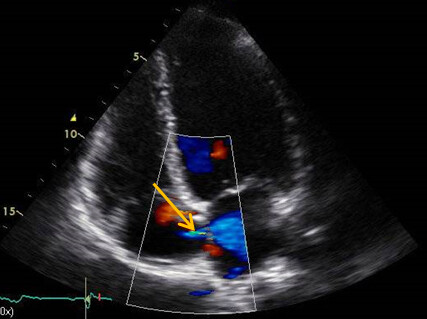

Im Farbdoppler fiel ein minimaler Links-Rechts-Shunt auf der Vorhofebene auf, wobei dieser Befund evtl. auch einem Artefakt entsprechen konnte (Abb. 1B). Rechtsherzbelastungszeichen ließen sich nicht dokumentieren.

Abb. 2: Rechtsherz Eckokardiografie, Credit: Perings